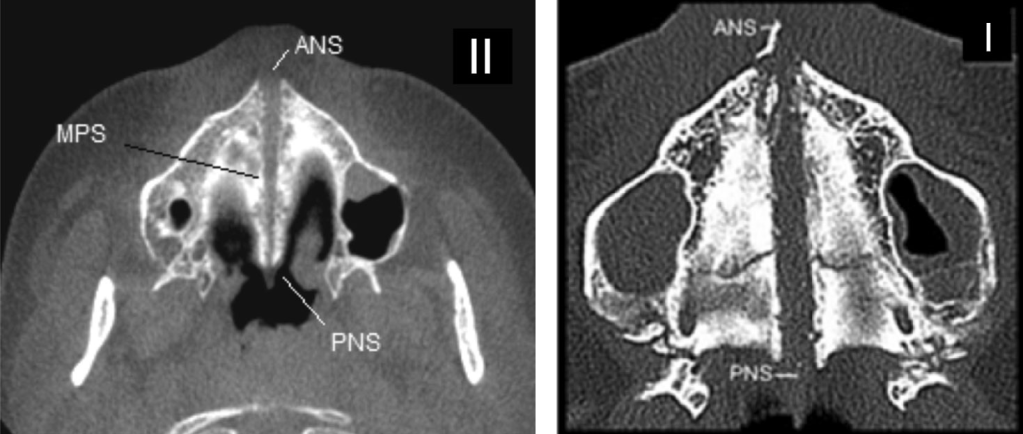

Thicker bone represents a better anchorage for the screws, reducing the risk of screw dragging. For this reason, doctors prefer to place the appliance more anteriorly in the midpalatal segment to reduce the risks of failure. The anterior segment also presents less resistance from other surrounding structures, thus more anteriorly the appliance is placed, more expansion can be achieved in the anterior segment. However, the posterior part has a higher resistance, because it is more engaged with other surrounding structures (for example think about the engagement of the zygomatic area, palatine and sphenoid bone that happens more posteriorly). This can thus result in a more conical/triangular or V-shaped expansion, which implies less benefits for the expansion of the airways (less nasal volume increase) and less midface changes.

An appliance placed more posteriorly increases the chances of a more parallel expansion of the midpalatal suture, thus resulting in more benefits for the nasal volume and midface. However, this presents also higher risks of failure since the resistance in that area of the palate is higher and the bone is less dense. The forces generated by the appliance have to overcome the resistance located in the midface such as the pyriform aperture pillars, zygomatic buttresses, pterygoid junctions, midpalatal suture, etc.

Bone density also plays a role in determining the type of anchorage for the miniscrews, aiding choosing between monocortical (perforation of the palatal cortical bone only) and bicortical (perforation of both the palatal and nasal cortical bone) insertion. When the monocortical insertion of miniscrews is used in individuals with thick suture or with great resistance to maxillary separation, distortions or folds may occur in the Temporary Anchorage Device during activation of the expanding screw. Bicortical insertion is recommended in these cases. Certain studies have also shown that bicortical insertion leads to higher skeletal expansion versus dental expansion when compared to monocortical.